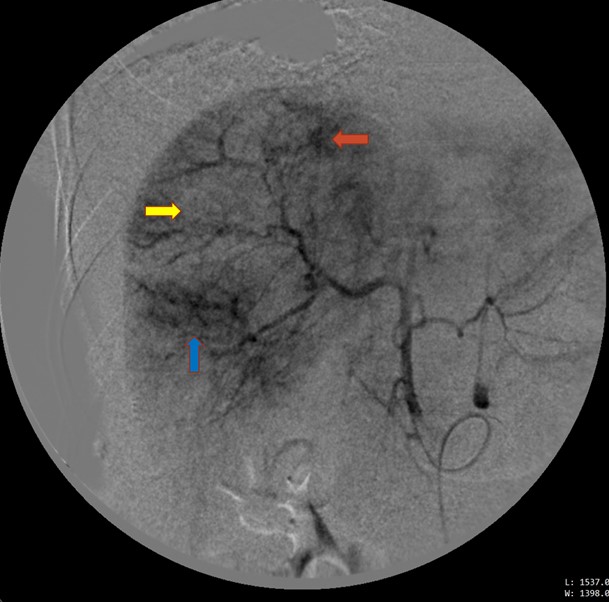

Bênh nhân được can thiệp nội mạch lúc 1:00 sáng ngày 03/04/2021. Chụp động mạch gan chung thấy ổ xuất huyết hoạt tính từ nhánh HPT VIII và nghi ngờ ở HPT VI, tương ứng với các vùng khuyết tưới máu. Chọn lọc nhánh HPT VIII bằng microcatheter, nút mạch bằng gelfoam. Chọn lọc nhánh HPT VI, nút mạch theo kinh nghiệm (empiric embolization) bằng gelfoam.

Hình 2. Chụp động mạch gan chung thấy hình ảnh xuất huyết từ nhánh HPT VIII (mũi tên đỏ), nghi ngờ xuất huyết từ nhánh HPT VI (mũi tên xanh), nhiều vùng khuyết tưới máu nhu mô ở gan phải (mũi tên vàng).